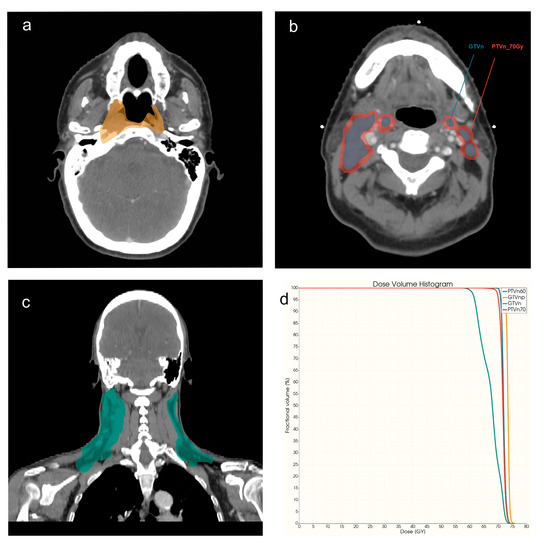

| VOIs | Descriptions of VOI | Imaging Modalities/Images |

|---|---|---|

| GTVnp | Gross tumor volume of primary NPC tumor | CECT, cT1WI, T2WI, DVH |

| GTVn | Metastatic lymph nodes area | CECT, DVH |

| PTVn_70Gy | Regions of nodal planning target volume with | DVH |

| the prescribed dose level of 70Gy | ||

| PTVn_60Gy | PTVn with the prescribed dose level of 60Gy | DVH |